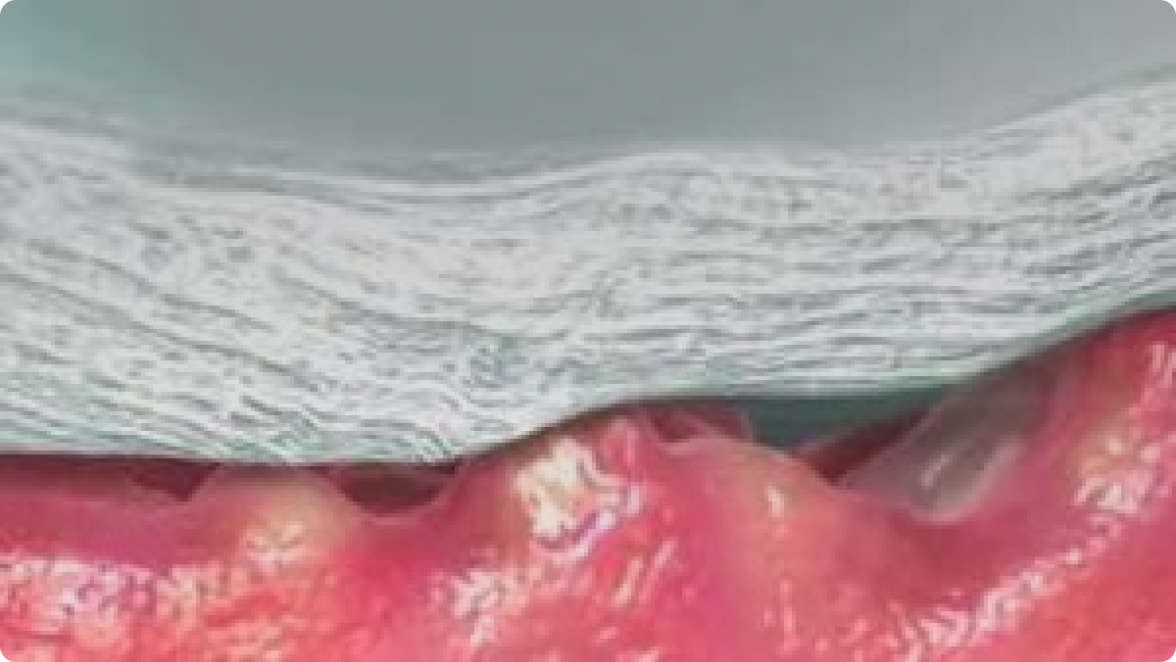

Intimate Contact

Contours